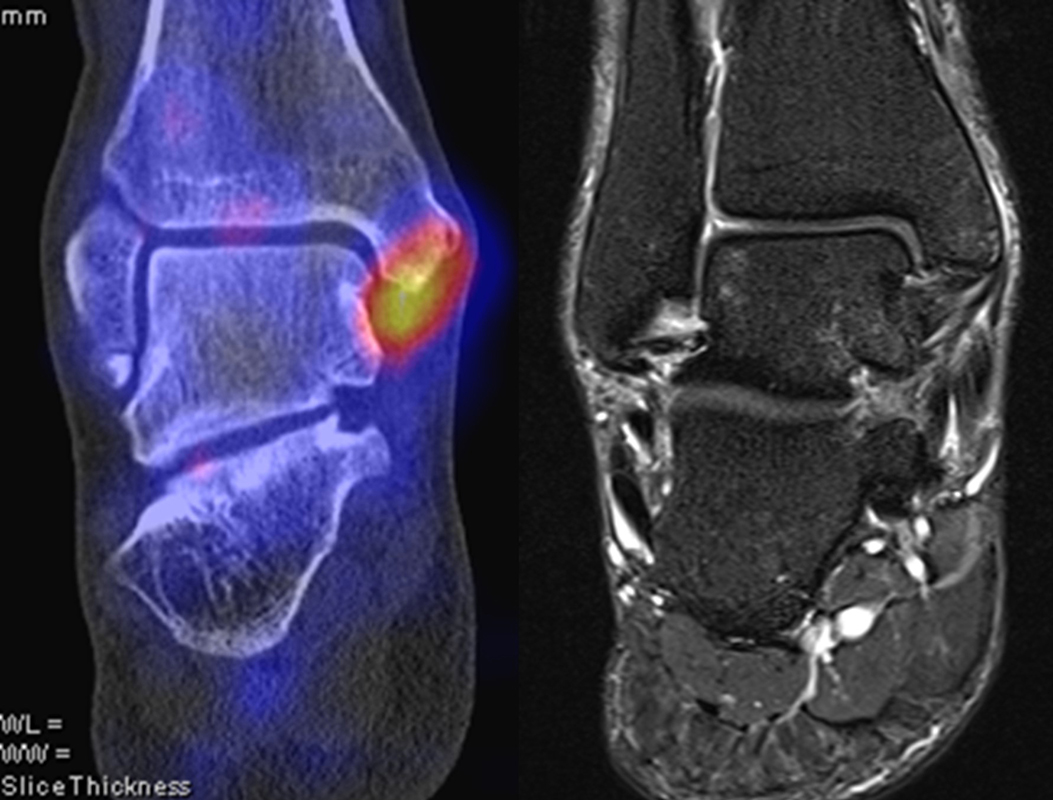

Osteonekrosen

Abbildung 9.2.a bis d: SPECT/CT zur Beurteilung der Knochen-Vitalität bei einer Talusnekrose. 5 Jahre zuvor während der Arbeit war die Patientin beim Treppensteigen umgeknickt und zog sich Außenbandrupturen zu. Nachfolgend persistierende Beschwerden mit Entwicklung einer Talusnekrose. Frage nach Vitalität und Ausdehnung der Nekrose. Deutliche bis intensive Traceranreicherung im Bereich des linken Talus. Im SPECT/CT befindet sich der Hypermetabolismus in allen Abschnitten des Talus mit relativer Aussparung eines sich demarkierenden Fragmentes lateral, was die laterale Talusschulter umfasst, die Größe beträgt transversal ca. 23 x 16 mm. In diesem Fragment relativ homogene Skelettstruktur, diese Befunde weisen auf eine trophische bzw. nekrotische Störung des Talus hin mit einem sich demarkierendem Fragment, welches die laterale Talusschulter beinhaltet.

Die Abbildung 9.3.a bis d zeigt ein weiteren Fall mit einer SPECT/CT zur Beurteilung der Knochen-Vitalität bei einer Talusnekrose. Die Bilder zeigen eine abgelaufene Nekrose mit zystischen Resorptionen des linken Talusdoms bei nachweislich erhaltener Vitalität der umgebenden Knochenabschnitte aufgrund des hier überall deutlich erhöhten Knochenmetabolismus (= inkomplette Restitutio). Aufgrund der nachweislich erhaltenen Vitalität konnte erfolgreich eine Knochen-Transplantation erfolgen.Deutlich geringer ausgeprägte nekrotische Veränderungen auch im rechten Talusdom bei hier weitgehend erhaltenen Gelenkkonturen.